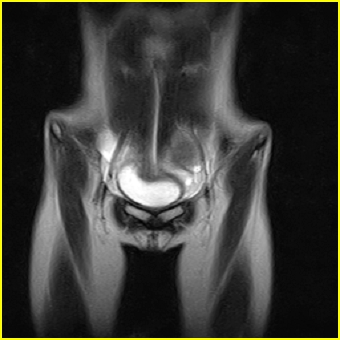

女、15岁、下腹疼痛2天,排尿困难1天。查体:处女膜闭锁,距处女膜约4至5cm处扪及一约5cm直径的圆形包块,张力较高,触痛明显、欠活动。b超提示子宫增大伴宫内增强回声团。

影像意见:子宫直肠陷凹积血。

更正影像意见:阴道积血。

处女膜闭锁,阴道积血

处女膜闭锁,阴道积血,子宫积血.

阴道积血,子宫积血.

子宫及阴道积血。

处女膜闭锁,伴子宫及阴道积血.